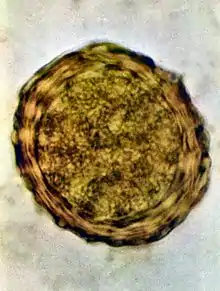

Fertile egg as can be seen in a microscope

Ascaris lumbricoides is characterized by its great size. Males are 2–4 mm (0.08–0.2 in) in diameter and 15–31 cm (5.9–12 in) long. The male's posterior end is curved ventrally and has a bluntly pointed tail. Females are 3–6 mm (0.1–0.2 in) wide and 20–49 cm (7.9–19 in) long. The vulva is located in the anterior end and accounts for about one-third of its body length. Uteri may contain up to 27 million eggs at a time, with 200,000 being laid per day. Fertilized eggs are oval to round in shape and are 45–75 μm (0.0018–0.0030 in) long and 35–50 μm (0.0014–0.0020 in) wide with a thick outer shell. Unfertilized eggs measure 88–94 μm (0.0035–0.0037 in) long and 44 μm (0.0017 in) wide.[9]